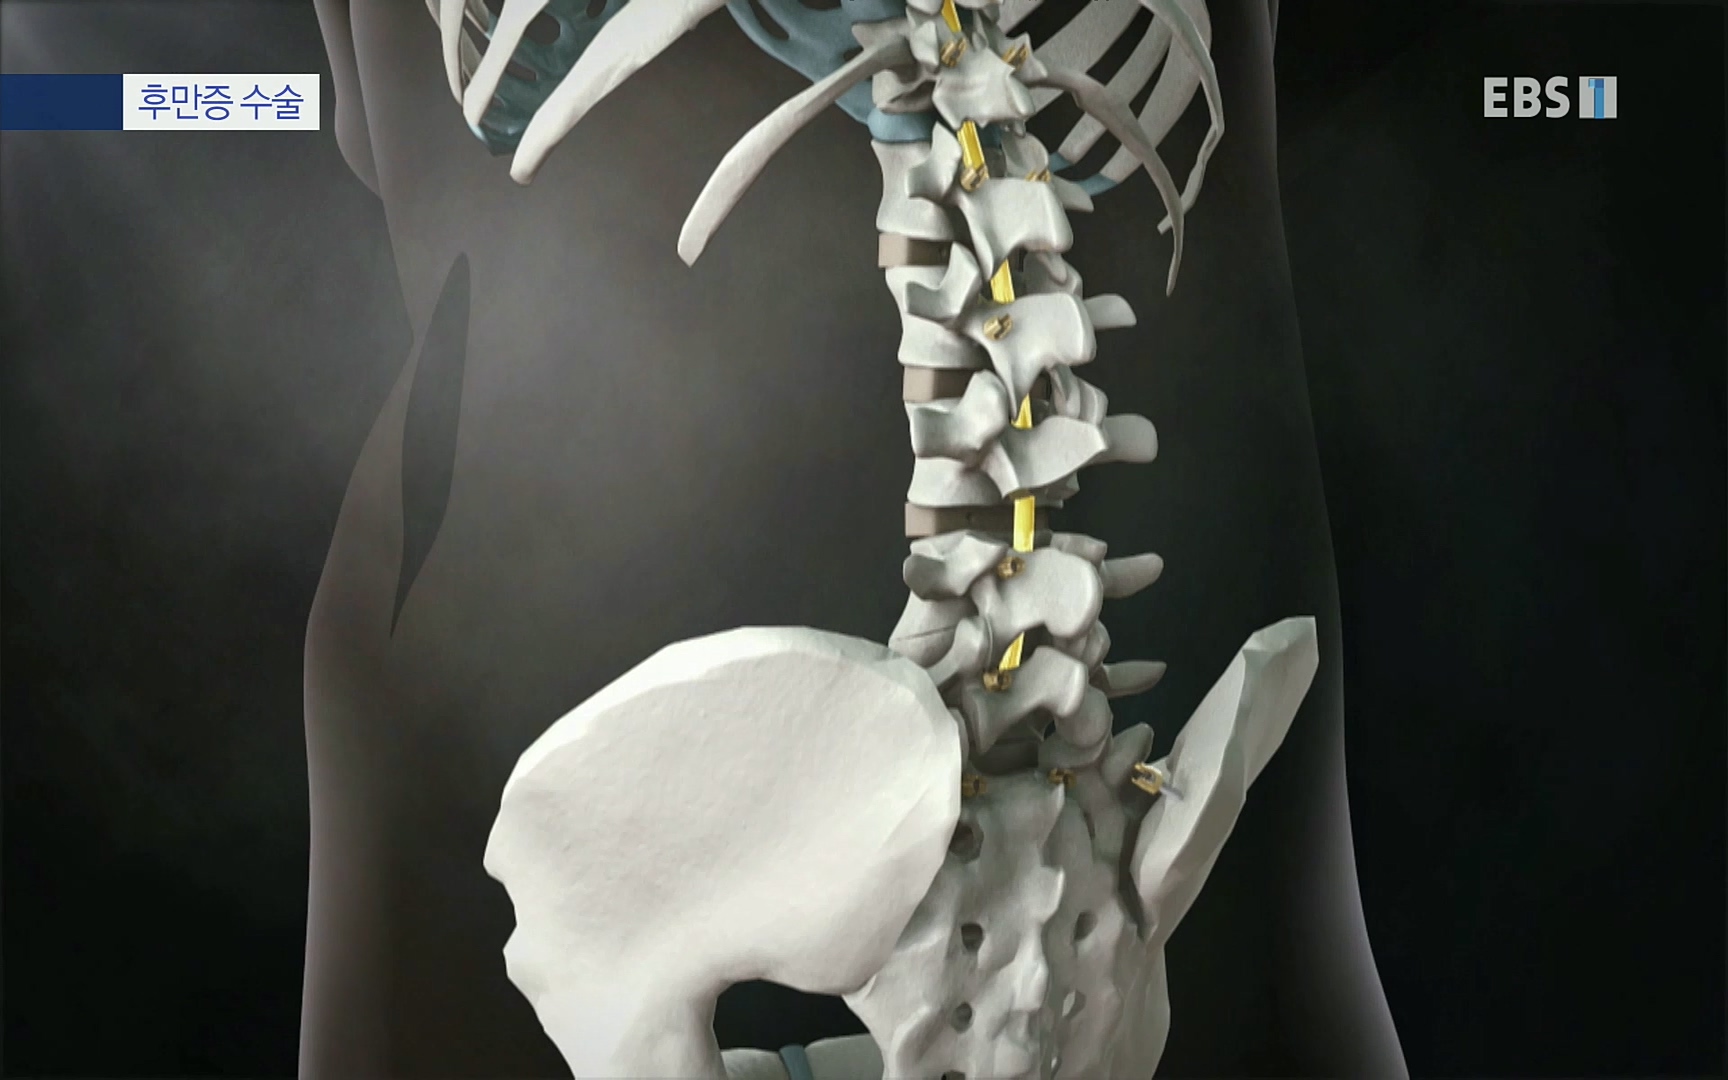

석세일 명예교수 정형외과 전문의 ·1995년 세계 최초 측만증에 척추경 나사못삽입술 시도 ㆍ척추변형에 대한 척추 후방 절제술, 척추 회전술 개발